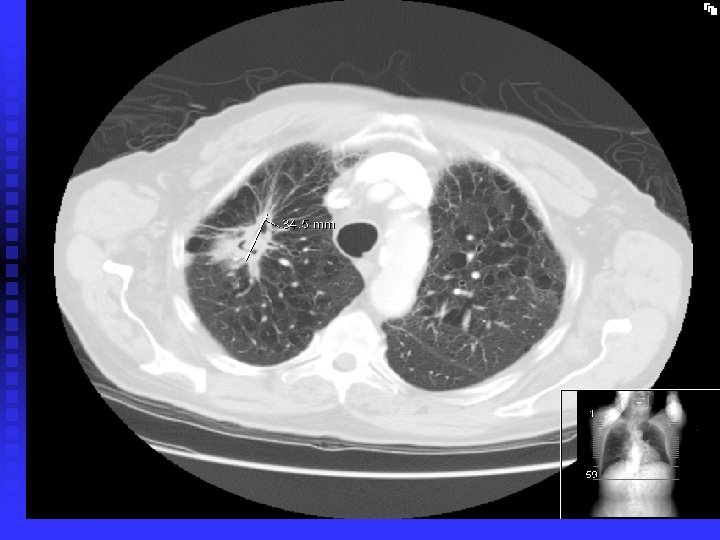

Case 3 56 year old woman, ex smoker, large goitre n Found to have a Nodule (Solitary pulmonary nodule) on CT scan = incidental n Interval scan if nodule < 1 cm or looks benign for up to 2 years n PET scan +/ CT guided biopsy if > 1 cm n If suspicious, then can consider wedge resection or lobectomy n